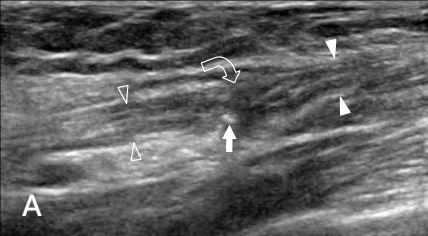

在高端显微镜下,医生像拆除“水泥”一样,精细地松解骨折周围压迫神经的坚硬瘢痕组织,并将神经从卡压处移到更安全、柔软的位置,为它创造一个良好的愈合环境。

这是技术的核心。在松解修复后,向患者受损部位植入一根小巧的 “临时脊髓神经电刺激器测试电极”。它类似一个智能的“神经起搏器”,通过电极向受损的尺神经发送温和的微量电脉冲。